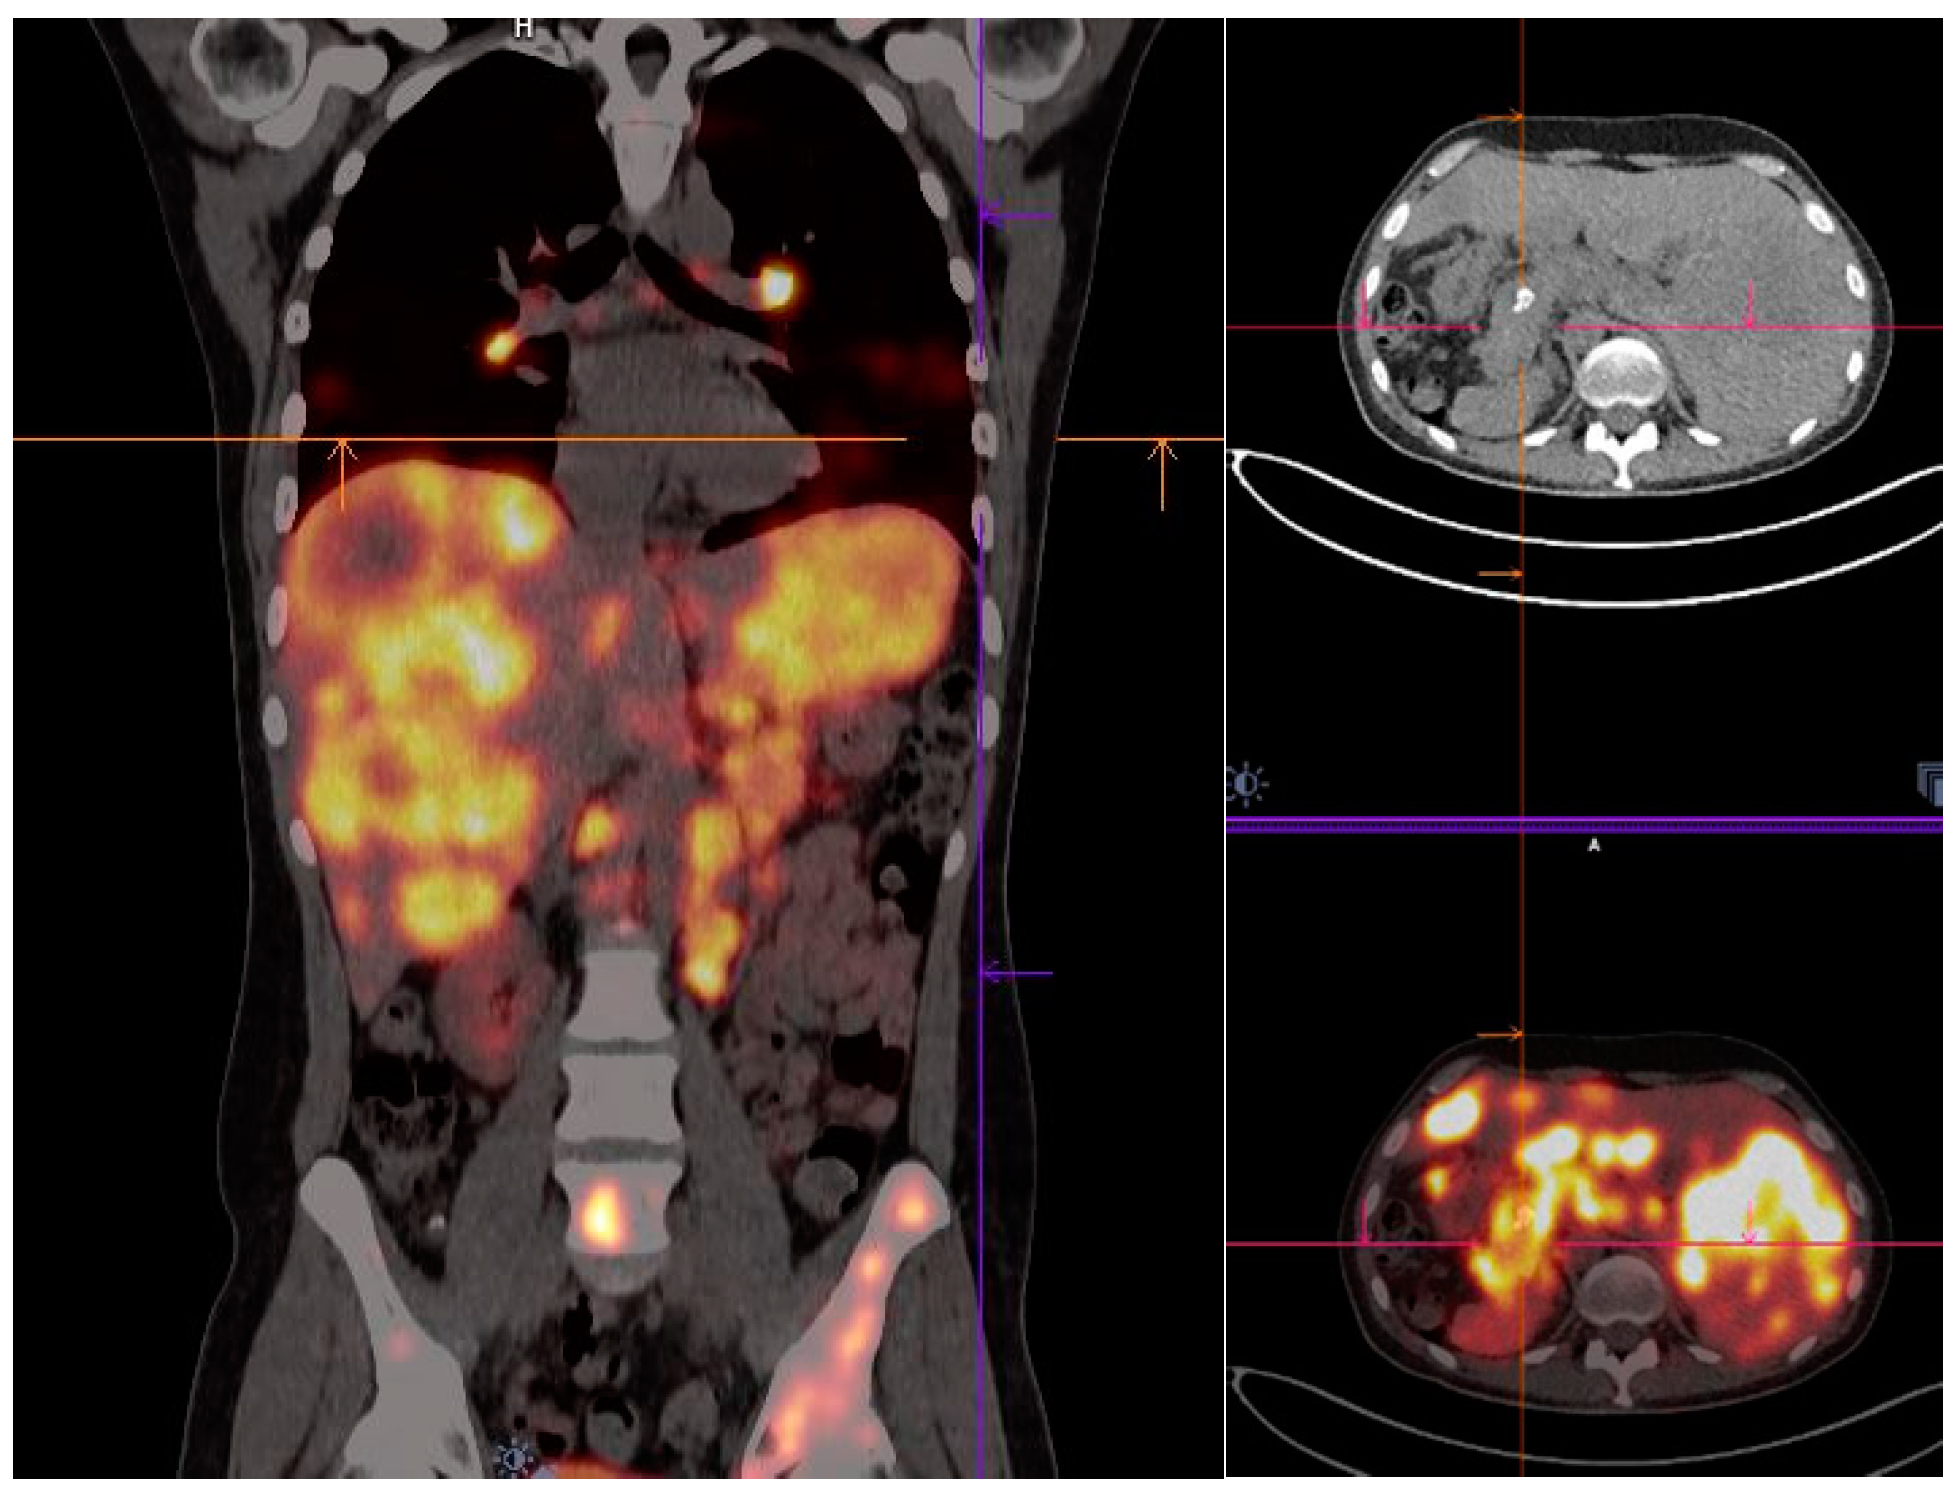

- Mirzaei, S.; Revheim, M.-E.; Raynor, W.; Zehetner, W.; Knoll, P.; Zandieh, S.; Alavi, A. 64Cu-DOTATOC PET-CT in patients with neuroendocrine tumors. Oncol. Ther. 2020, 8, 125–131. [Google Scholar] [CrossRef] [Green Version]

| [64Cu]Cu-DOTA-TOC | NET | 33 | 2019 | High detection rate and high target to background ratio in images raised [64Cu]Cu- DOTA-TATE as a promising and safe radiolabeled SST derivative for NET detection | [22] |